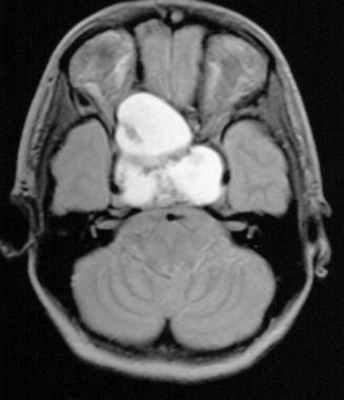

МРТ при кисте кармана Ратке

МР-картина может быть очень различной (см. изображения ниже). Несмотря на то, что не было определено никаких специфичных МРТ-признаков, большинство можно разделить на следующие две группы:

1) С низкой интенсивностью сигнала на Т1-взвешенных изображениях и высокой интенсивностью на Т2-ввешенных изображениях

2) С высокой интенсивностью сигнала на Т1-взвешенных изображениях и вариабельной интенсивностью сигнала на Т2-взвешенных изображениях

![f4]()

Т1-взвешенное сагиттальное изображение, полученное до контрастного усиления: видна хорошо определяемая киста в зоне турецкого седла, изоинтенсивная спинно-мозговой жидкости. Отмечается соответствующая норме высокая интенсивность сигнала задней доли гипофиза сзади.

![f5]()

На Т1-взвешенном корональном изображении она видна рамером чуть менее сантиметра в центральной части турецкого седла. Слегка гиперинтенсивна по сравнению со спинно-мозговой жидкостью.

![f6]()

На этом Т2-взвешенном изображении она изоинтенсивна спинно-мозговой жидкости.

![f7]()

Крупная гиперинтенсивна по сравнению со спинно-мозговой жидкостью на аксиальном протонно-взвешенном изображении. Отмечается расширение турецкого седла с латеральным отклонением чуть заслоненной, но проходимой кавернозной частью внутренней сонной артерии.

Содержимое первой группы напоминает спинномозговую жидкость (СМЖ). Во второй группе усиление сигнала на Т1-взвешенных изображениях связано с высоким уровнем содержания мукополисахаридов, что, как считается, является следствием увеличения числа муцин-секретирующих клеток в стенке, а также повышенной активности этих клеток.

Редкие случаи высокой интенсивности сигнала на Т1-взвешенных изображениях и низкой интенсивности на Т2-взвешенных изображениях связаны с сочетанием различных факторов, включающих в себя наличие мукополисахаридов, застарелое кровоизлияние, значительное содержание холестерина или клеточного детрита стенки кисты. Они практически всегда однородны по интенсивности сигнала, в то время как для других патологических образований, таких как краниофарингеомы и геморрагические аденомы, чаще характерна гетерогенность интенсивности сигнала.

Имеют тонкую стенку, которая может контрастироваться при вводе контрастных веществ на основе гадолиния. Различные варианты контрастирования гадолинием могут отражать плоскоклеточную метаплазию стенки или смещенную к периферии в виде ободка ткань гипофиза.